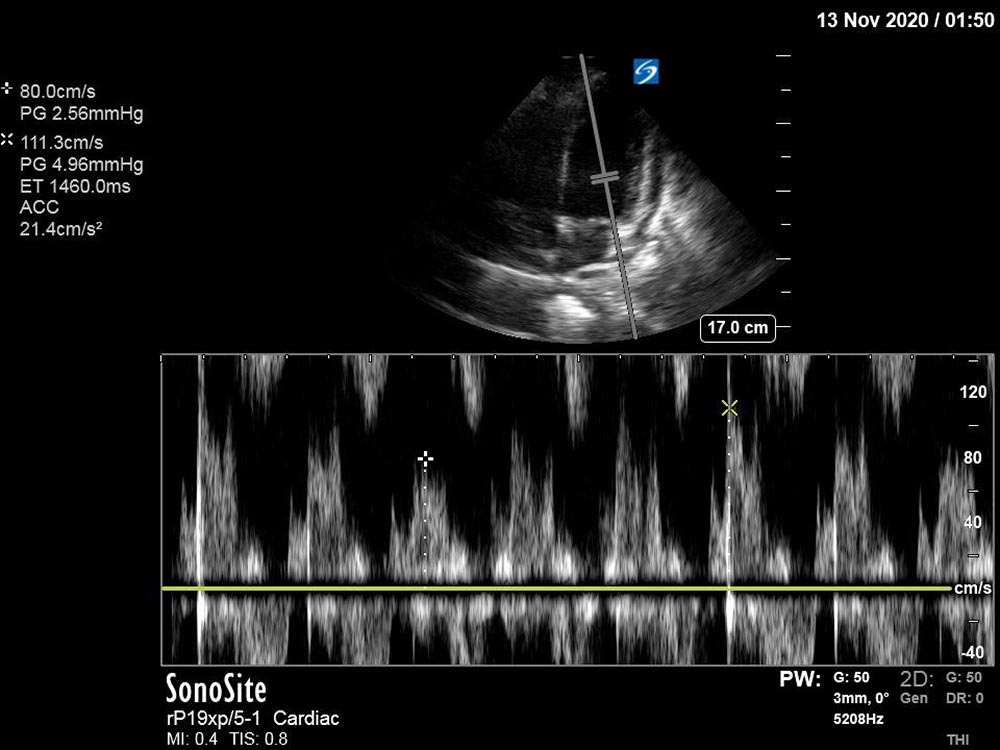

An elderly patient with multiple co-morbidities presents to the ED with dyspnea and is found to be in obstructive shock secondary to cardiac tamponade. The learner should perform a primary survey, recognize the need for emergent intervention, and rapidly obtain key diagnostic data, including performance of a bedside ultrasound. Upon recognizing that the patient has cardiac tamponade, appropriate management should be initiated, including resuscitation and emergent pericardiocentesis.